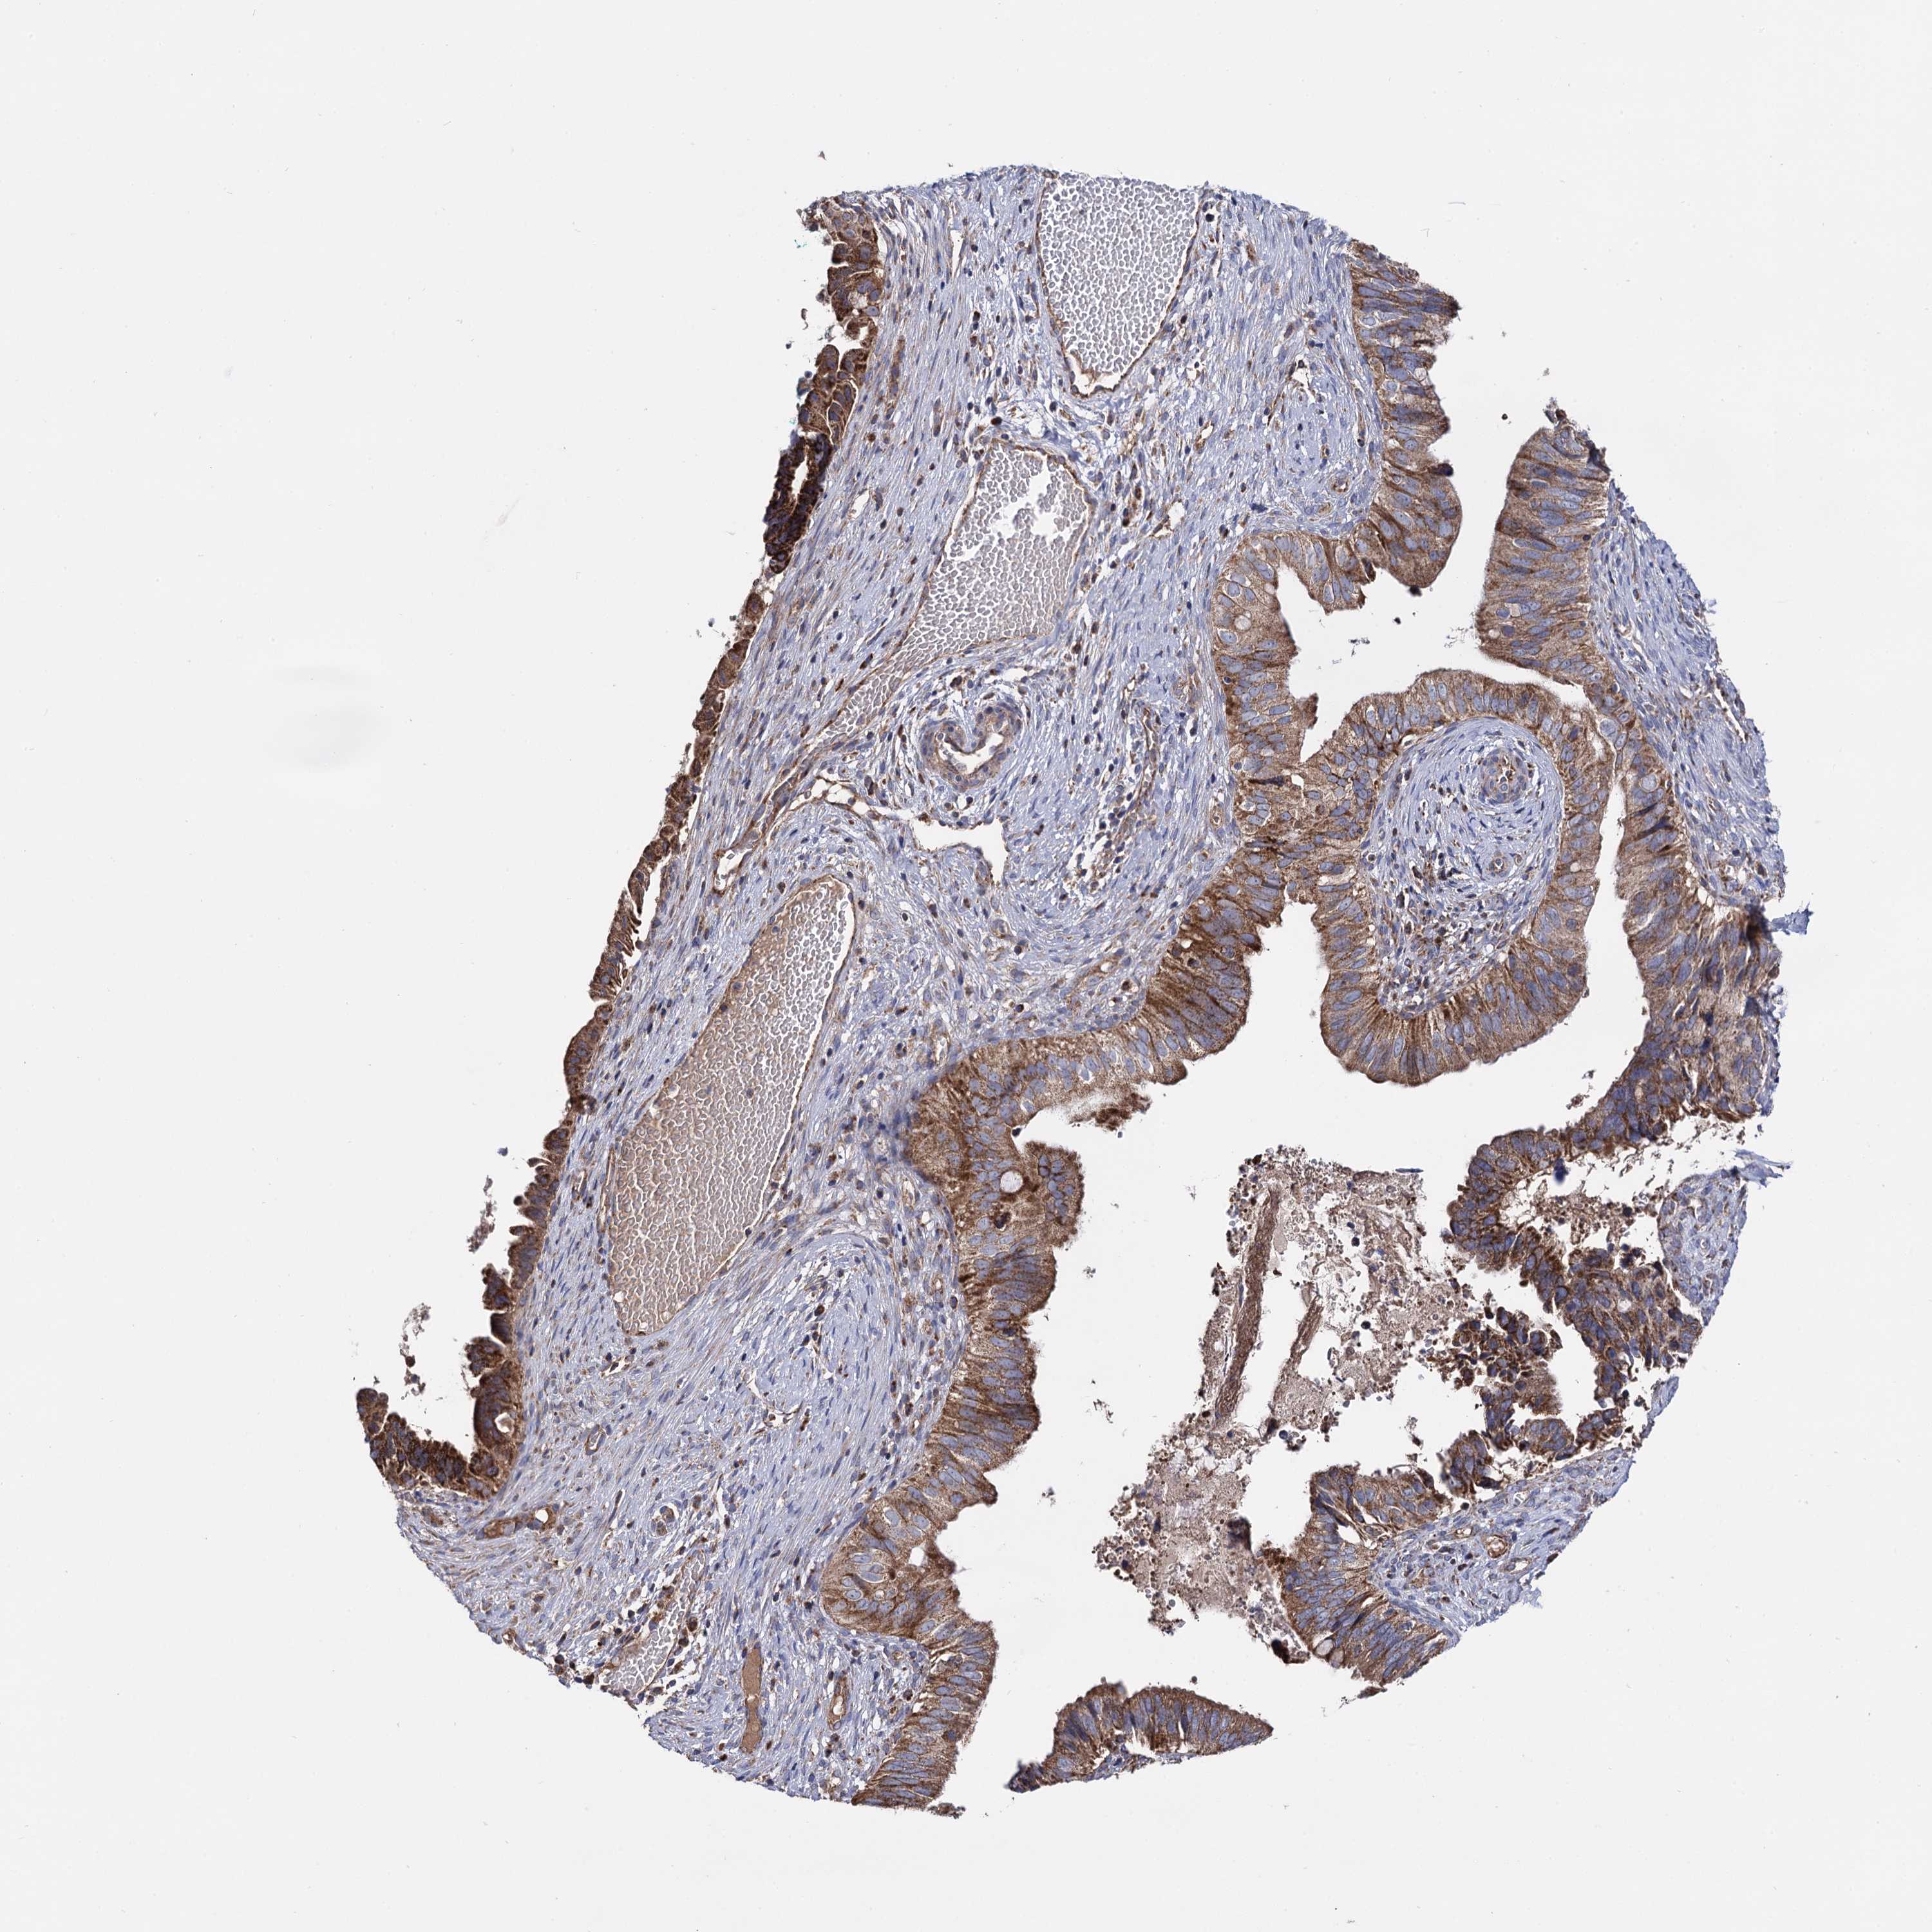

CERVICAL CANCER - Protein expressioni

A mouse-over function shows sample information and annotation data. Click on an image to view it in a full screen mode. Samples can be filtered based on level of antibody staining by selecting one or several of the following categories: high, medium, low and not detected. The assay and annotation is described here.

Note that samples used for immunohistochemistry by the Human Protein Atlas do not correspond to samples in the TCGA dataset.

Antibody stainingi

Antibody staining in the annotated cell types in the current human tissue is reported as not detected, low, medium, or high, based on conventional immunohistochemistry profiling in selected tissues. This score is based on the combination of the staining intensity and fraction of stained cells.

Each image is clickable and will lead to virtual microscopy that enables deeper exploration of all samples and also displays staining intensity scores, fraction scores and subcellular localization as well as patient and tissue information for each sample.

Antibody HPA040845

Staining

High

Medium

Low

Not detected

Intensity

Strong

Moderate

Weak

Negative

Quantity

>75%

75%-25%

<25%

None

Location

Nuclear

Cytoplasmic/membranous

Cytoplasmic/membranous,nuclear

Squamous cell carcinoma, NOS

Adenocarcinoma, NOS